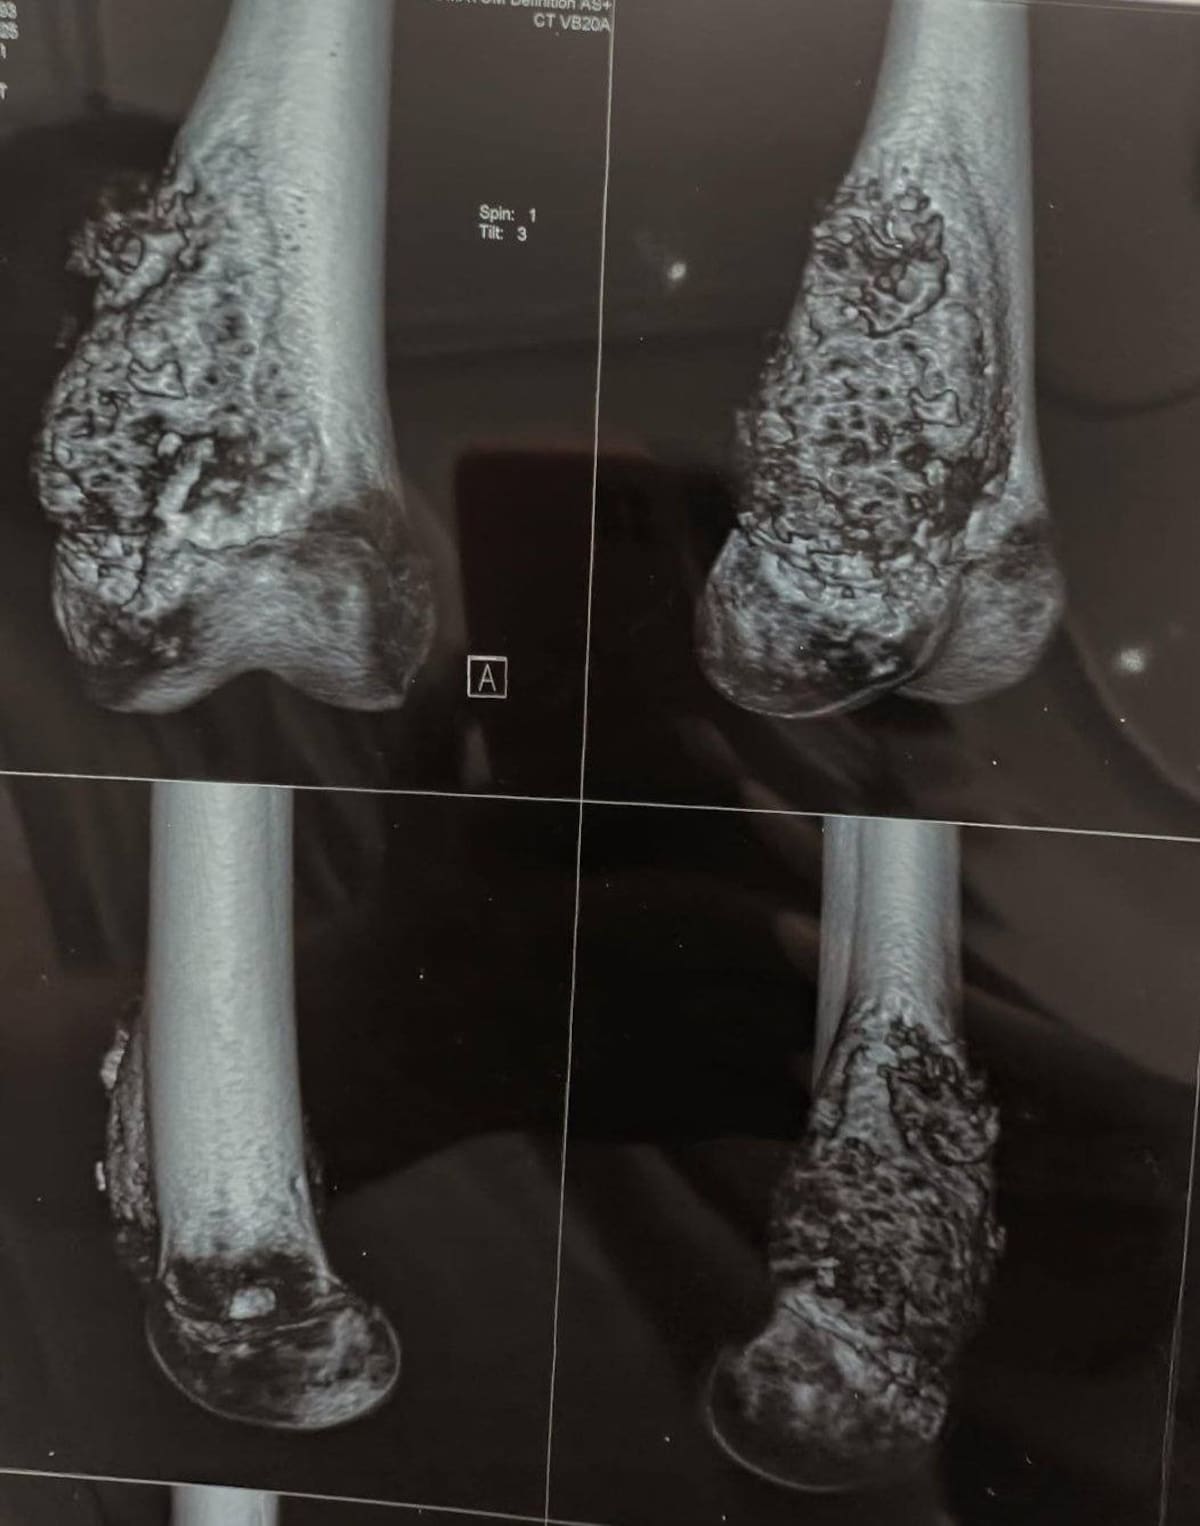

Actualmente, con solo 12 años, ya ha superado una cirugía para retirar el tumor en su rodilla y parte del fémur que estaba afectado.

“En la cirugía le cortaron el fémur y le pusieron una prótesis que conecta su pierna con la tibia, es decir, la parte de abajo. Pero las quimioterapias siguen; ya vamos en el último ciclo y, Dios mediante, terminamos a principios de abril.